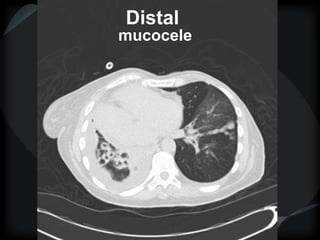

Bronchiectasis

central

Distal

mucocele

Bronchiolarectasis

DPB